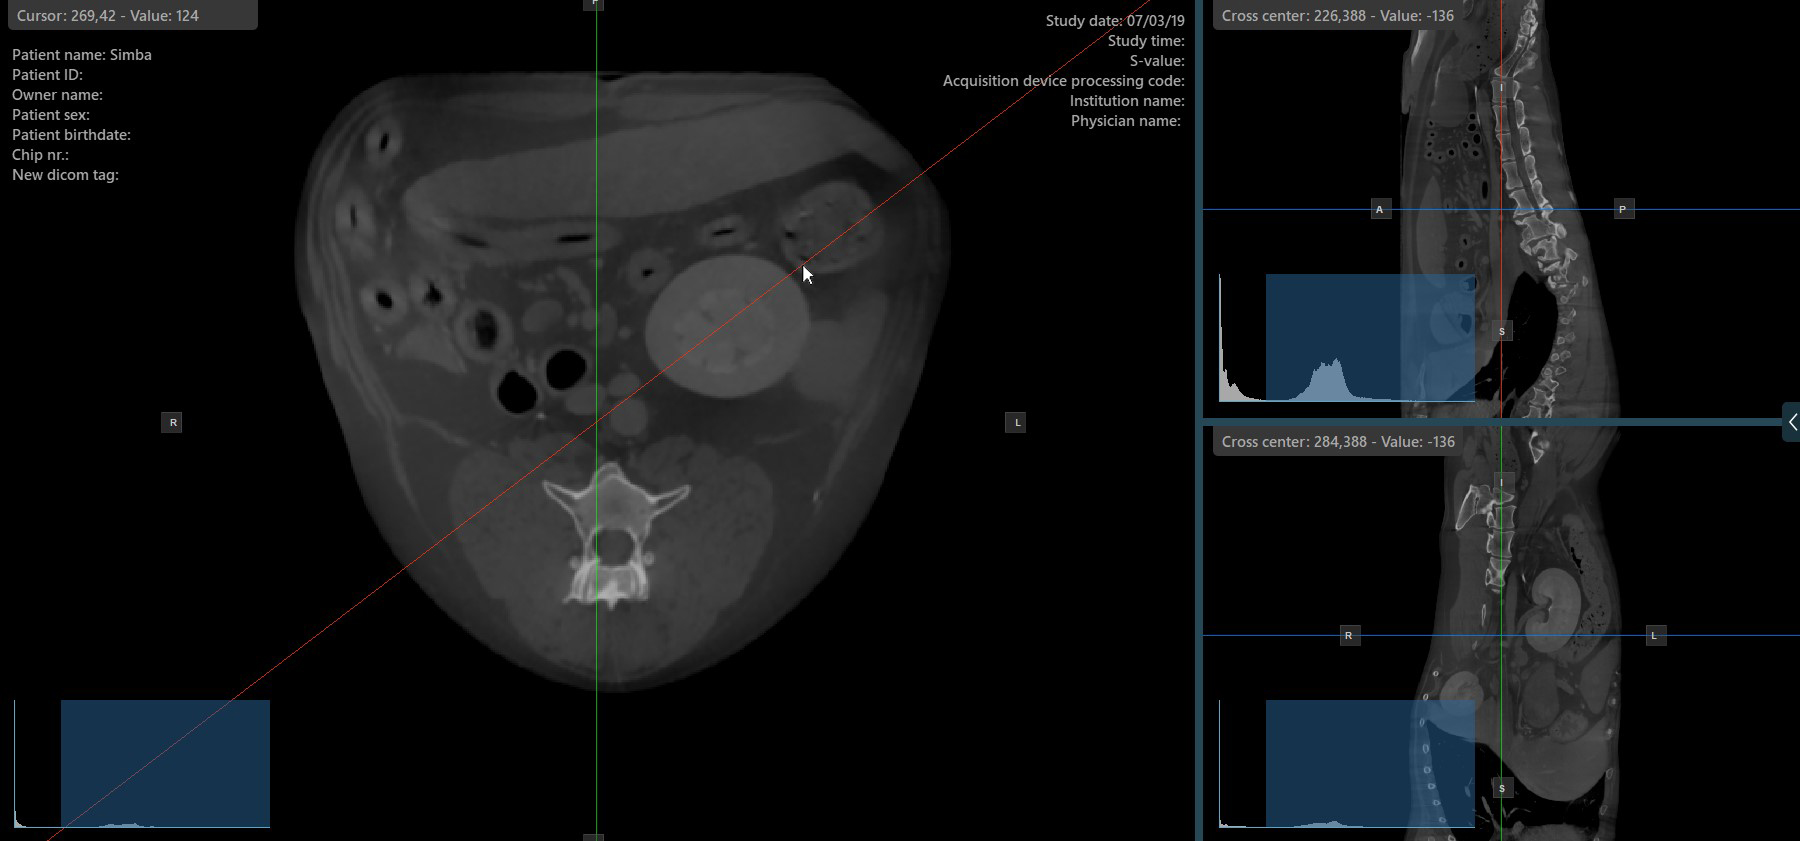

Change Slicer Rotation¶

Altering the rotation of a slicer will change the orientation of the corresponding image planes. Individual slicers can be selected by using the Select Item (Default) tool, assigned to the right mouse button by default.

Once the specific slicer is selected, drag the slicer in the desired direction to rotate it. The corresponding image plane’s orientation changes accordingly.

By default, each slicer can be rotated separately. The corresponding icon in the left toolbar of the CT Viewer will be deselected when the slicers are rotated individually.